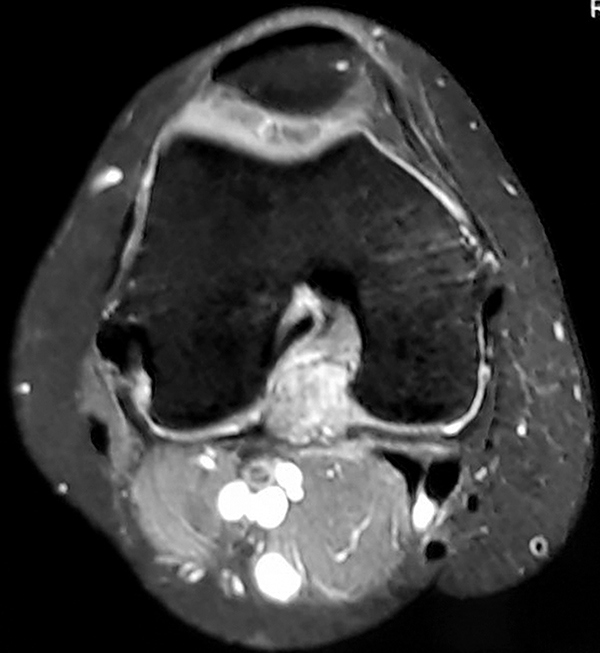

Paciente de 46 años de edad de sexo femenino consulta por dolor de rodilla derecha de dos meses de evolución, asociada a aumento de volumen, con limitación progresiva de la capacidad de realizar actividades cotidiana con episodio de bloqueo articular que resolvió espontáneamente. Al examen físico, se observa limitación de la extensión completa de 10º asociada a marcha claudicante. A la palpación se constata una pequeña masa tumoral en hueco poplíteo, dolorosa, duroelástica adherida a planos profundos. Se solicitó RMN donde se observa una masa heterogénea en T1 y T2 de naturaleza intraarticular localizada en intercóndilo posterior de la rodilla (figs. 1 y 2). Se planteó como diagnóstico diferencial sinovitis vellonodular pigmentaria o tumor tenosinovial de células gigantes. Por protocolo de servicio y para ir a la cirugía definitiva con diagnostico de certeza se realizó una biopsia guiada por TAC. La histopatología confirmó nuestra segunda hipótesis diagnóstica.

Figura 1 y 2: Localización tumoral retro LCP en cortes axiales y sagitales.